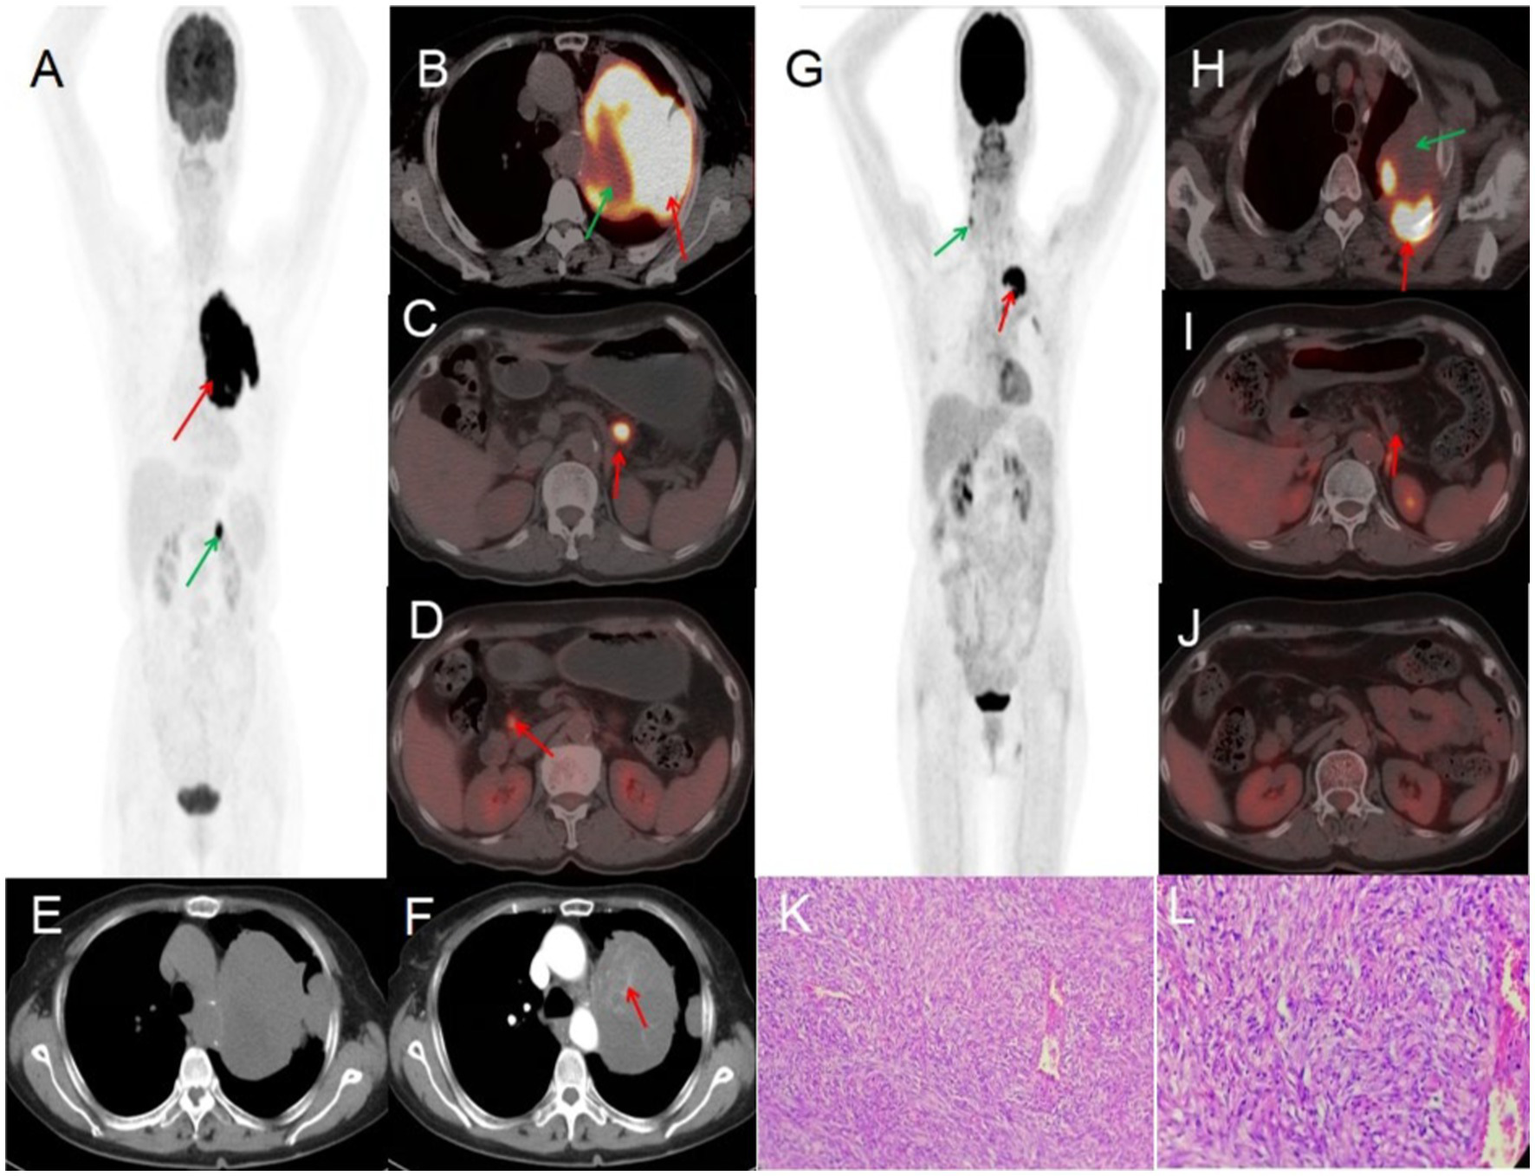

A 70-year-old female presented with symptoms of chest tightness, discomfort, and occasional non-productive cough on March 13, 2022. She reported mild chest pain but denied shortness of breath, chills, fever, dizziness, headache, abdominal pain, or distension. The patient was admitted to Jiangxi Provincial People’s Hospital for further evaluation and management. Since symptom onset, she maintained normal mental status, appetite, sleep patterns, and bowel and bladder function without significant weight changes. The patient had no history of chronic disease and a history of other types of tumor. Tumor markers were within normal limits, except for slightly elevated levels of CYFRA21-1 3.50 (0–3.3) ng/mL, NSE 22.77 (0–16.3) ng/mL, and CEA6.98 (0–6.5) ng/mL. Lung CT revealed a large, ill-defined soft tissue density mass in the left upper lung with heterogeneous internal density, including areas of low-density necrosis, and irregular enhancement on contrast-enhanced scan. Abdominal CT showed nodular shadows posterior to the pancreatic body and adjacent to the pancreatic head, demonstrating mild to moderate enhancement on contrast imaging. CT findings were consistent with a malignant tumor. 18F-FDG PET/CT demonstrated a large, heterogeneously dense soft tissue mass in the left upper lobe with multiple patchy low-density areas, indistinct margins, loss of fat planes between the mass and mediastinum, encasement of the left upper pulmonary artery, and adjacent pleural thickening and adhesion. The mass measured 88 × 108 mm with markedly increased FDG uptake (SUVmax 23.2), while the necrotic regions showed no FDG avidity. Two pancreatic nodules—near the head and posterior to the body of the pancreas—also exhibited elevated FDG uptake (SUVmax 13.2). Preoperative PET/CT suggested pulmonary malignancy with intraperitoneal metastasis. A CT-guided needle biopsy was performed, with histopathology confirming a solitary fibrous tumor (SFT) of the left upper lung, characterized by high cellularity and active proliferation. Due to the large mass and abdominal metastasis, medical treatment was initiated after extensive consultation and comprehensive evaluation within the hospital. The patient was treated with bevacizumab 400 mg on day 1 and temozolomide 220 mg on days 1–5. After one treatment in this cycle, patients were treated with cindilizumab (200 mg) + alotinib (12 mg on days 1 to 14), supplemented with stomach protection, antiemetic, and immune correction therapy. After one year of treatment, the patient’s response was satisfactory: PET/CT scan demonstrated a significant decrease in the volume of the solitary fibrous tumor in the lungs following chemotherapy, along with a notable reduction in FDG uptake in the masses. No significant increase in FDG uptake was observed in intraperitoneal metastatic lesions located behind the pancreatic body or near the head of the pancreas, indicating that the active part of the lung tumor had been inactivated, and the activity of the intra-abdominal metastases had been completely suppressed. After multidisciplinary consultation, because the patient had signs of distant metastasis and a large primary tumor, she performed intraoperative lymph node dissection while surgical resection of the mass. Postoperative pathology revealed that a primary lung malignant solitary fibrous tumor was suspected, with no tumor involvement at the incisal margin of the bronchus. Regional lymph nodes showed no evidence of tumor metastasis in nine lymph nodes examined (two of which exhibited necrotizing granulomatous inflammation). The vascular tissue (artery wall) was examined and found to have fibrous tissue hyperplasia with glass change. The patient received comprehensive anti-tumor treatment post-surgery (see Figure 1).

Figure 1

Female, 70 years old, malignant pulmonary solitary fibrous tumors. (A) Whole body MIP. (B–D) Axial fusion. (E) Axial, non-contrast-enhanced CT. (F) Axial, enhanced CT-arterial phase. 18F-FDG PET/CT imaging findings: a large soft tissue mass was identified in the upper lobe of the left lung, exhibiting heterogeneous density with multiple patchy hypodense areas and ill-defined margins. The mass showed loss of the fat plane adjacent to the mediastinum, encasement of the left upper pulmonary artery, and associated pleural thickening and adhesions. On contrast-enhanced CT, the lesion demonstrated marked heterogeneous enhancement in the arterial phase, with internal septations and multiple enhancing vascular structures (arrow, F). The mass measured 88 × 108 mm in maximum dimensions and exhibited intensely increased metabolic activity, with a maximum standardized uptake value (SUVmax) of 23.2 (red arrow, B). No FDG uptake was observed in the central hypodense necrotic regions (green arrow, B). Additionally, two hypermetabolic nodules were noted in the pancreatic head and retropancreatic region (arrows, C,D), demonstrating an SUVmax of 13.2. (G) Whole body MIP. (H–J) Axial fusion. (K) H-E ×200. (L) H-E ×400. Follow-up 18F-FDG PET/CT imaging (post-chemotherapy). The previously documented solitary fibrous tumor of the lung demonstrated significant size reduction following one year of chemotherapy. Imaging findings: a heterogeneous, ill-defined mass (approx. 50 × 73 mm in maximal cross-section) persists in the left upper lobe, with adjacent pleural thickening and adhesions. Metabolic activity has markedly decreased, with residual FDG uptake localized to the posteromedial margin (SUVmax 10.8, red arrow, H). No significant metabolic progression was observed in the known intraperitoneal metastatic lesions (retropancreatic and pancreatic head regions, red arrows, I,J). A focal FDG-avid focus in the right neck was deemed non-specific (green arrow, G). Pathological correlation (microscopic features): tumor cells display mild to moderate atypia, with round to oval morphology and a predominant spindle-cell composition. The stroma exhibits collagen-rich fibrosis, focal myxoid degeneration, and scattered areas of mitotic activity and hypercellularity (K,L).